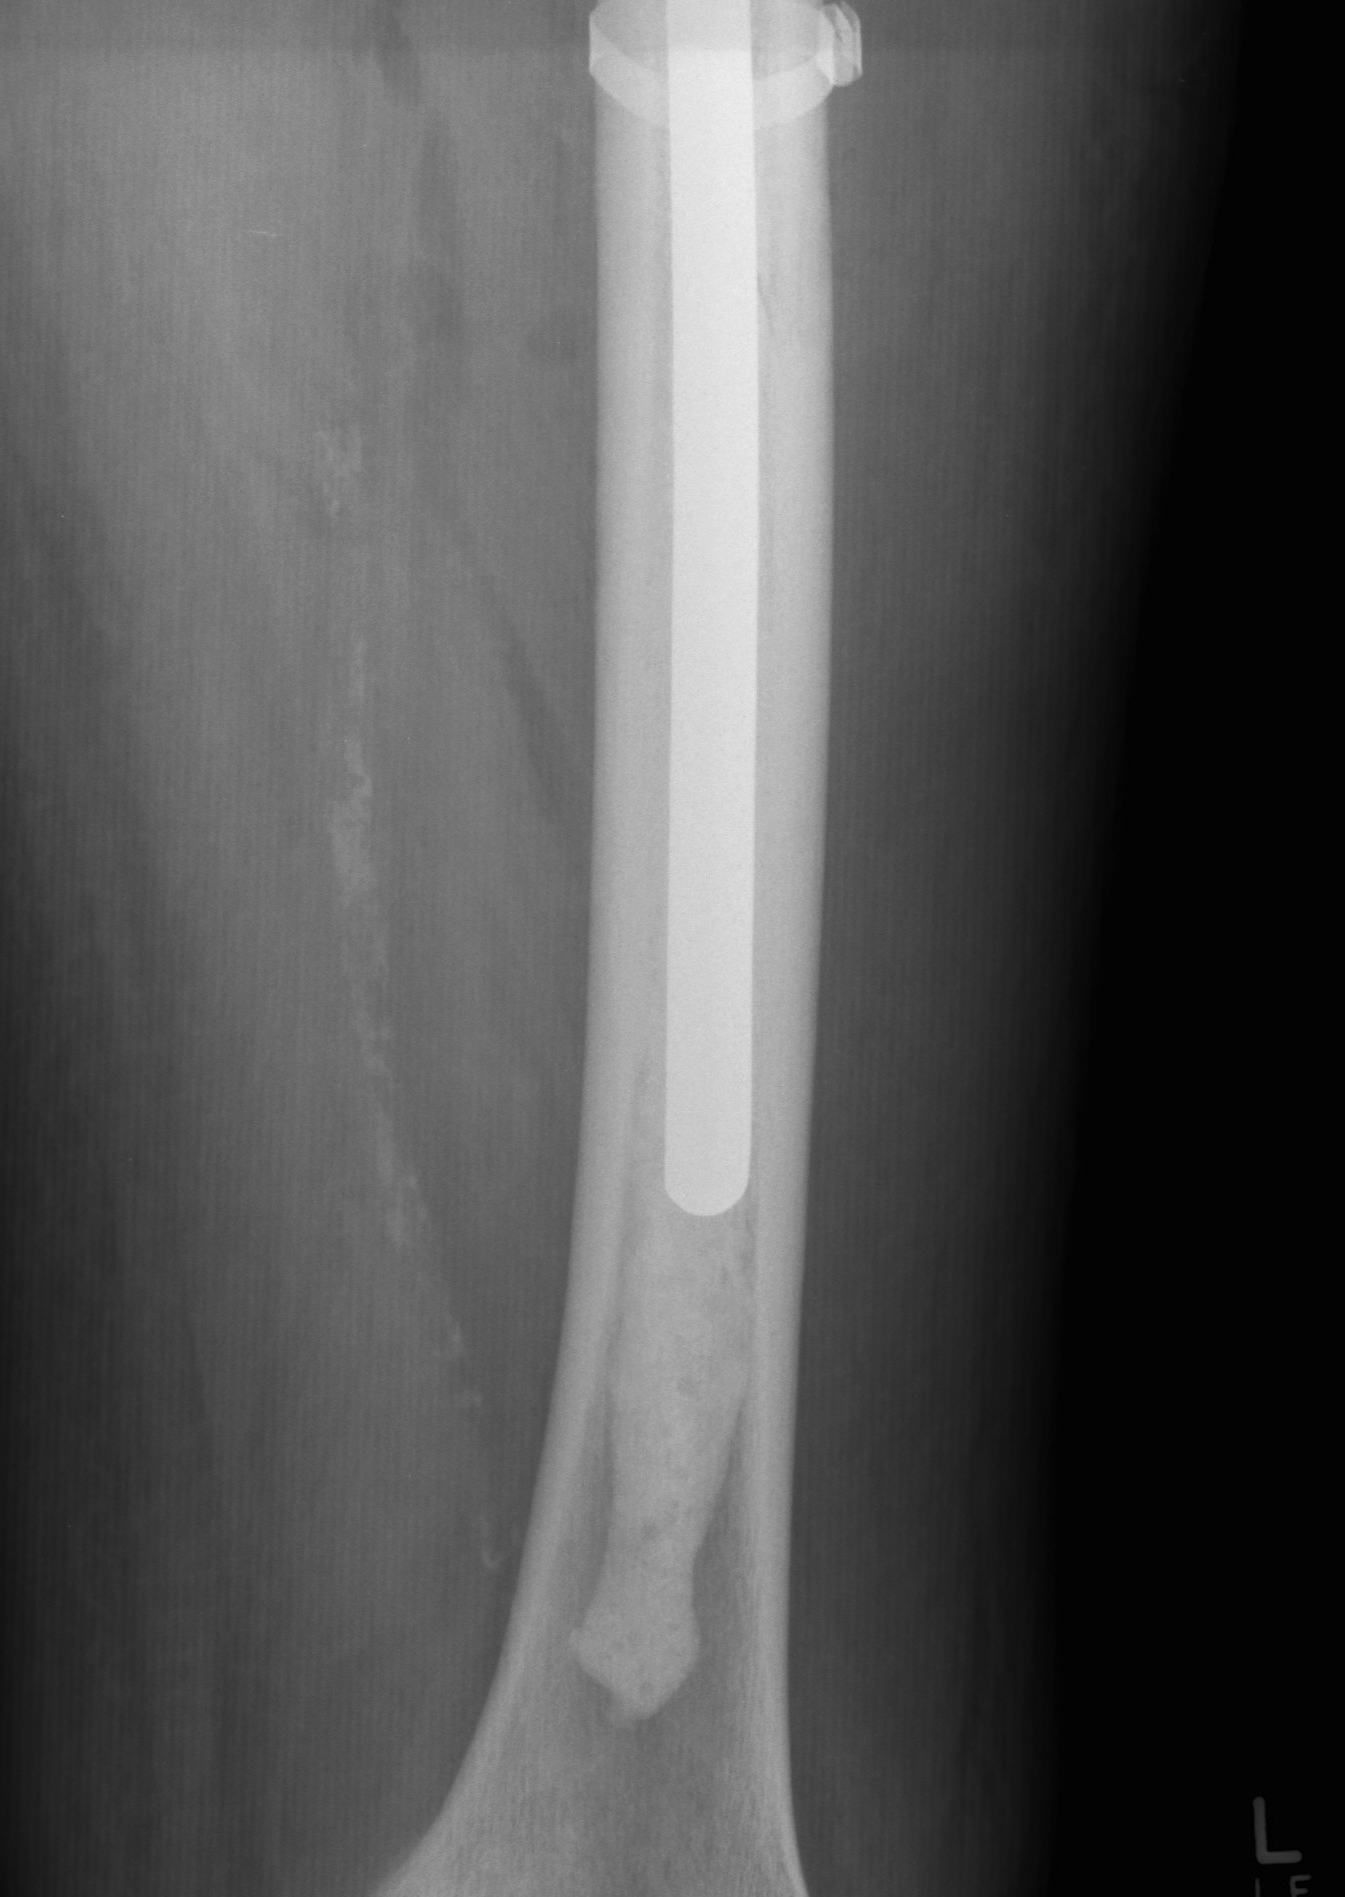

Long stem uncemented revision with cortical strut allograft

Long stem uncemented revision with plate + cortical struts